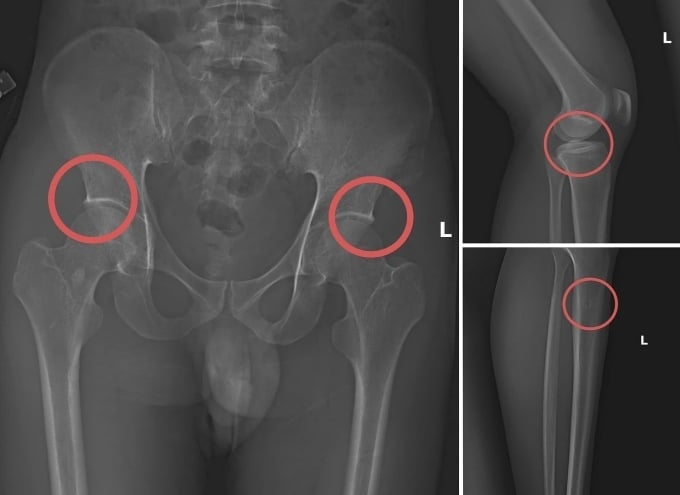

Đáng chú ý, C. trực tiếp thực hiện hành vi tiêm thuốc mê, rồi dùng kim tiêm, búa đinh để tác động vào xương người mua bảo hiểm, tạo nên các vết nứt, vỡ xương tương tự tai nạn thật. Khi thương tích đã tạo xong, C. tiếp tục hướng dẫn các đối tượng dựng hiện trường giả như điện giật ngã, trượt chân ngã suối nhằm hợp thức hóa bệnh án và hoàn thiện hồ sơ yêu cầu chi trả.

Các vết thương do Châu tự tạo nên. Ảnh: Công an cung cấp